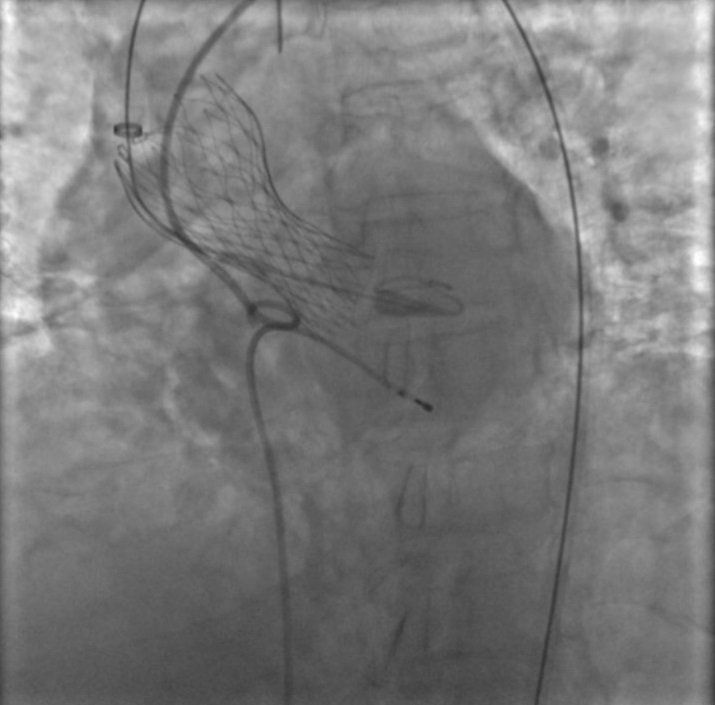

Dal 2010 al pensionamento è stato responsabile dell’unità di Emodinamica dell’Ospedale di Lecco, ove nel corso degli anni, oltre all’angioplastica coronarica, sono stati intrapresi anche più complessi trattamenti trans-catetere di cardiopatie strutturali: sostituzione aortica trans-catetere (TAVI), trattamento trans-catetere della mitrale ed interventi di chiusura di pervietà del forame ovale (PFO), difetti interatriali (DIA), difetti interventricolari (DIV) e dell’auricola sinistra ecc.